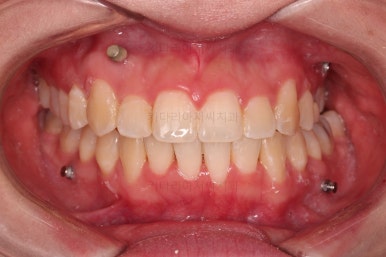

부산비대칭교정 마무리 때의 입안의 모습입니다.

가지런한 느낌은 좋지만 정중선 당연히 약간 안맞고요.

폭도 100%는 안맞아서 어금니쪽이 약간 애매한 교합이기도 했습니다.

하지만 이정도의 비대칭 상황에서 이정도의 교합은 교정만으로 할 수 있는 베스트가 아닌가 생각됩니다.

전후 비교 사진인데요.

입매가 비발치임에도 불구하고 매우 좋아졌고요.

치열과 교합도 매우 좋아졌습니다.

웃을 때 보이는 치열의 기울기도 좋아졌고요.

입을 다물었을 때 입술의 기울기도 처음보다는 좋아졌는데 앞서 말씀드린대로 뼈의 위치가 좋아졌다거나 뼈의 형태가 개선되어서 그런게 아니고요. 치열이 가지런해지고 입이 들어감으로서 입술이 다물어지는 편안한 정도가 바뀌면서 마치 입술의 비대칭까지 좋아진 듯한 착시효과가 생기는 것입니다.

비대칭은 여전히 비대칭입니다.

다만, 그 안에서 최대한 양호한 교합과 모양을 찾아가는 것이 이번 부산비대칭교정 치료의 목표였고, 그런 목표에서는 상당히 만족스럽게 치료가 끝났다고 판단됩니다.